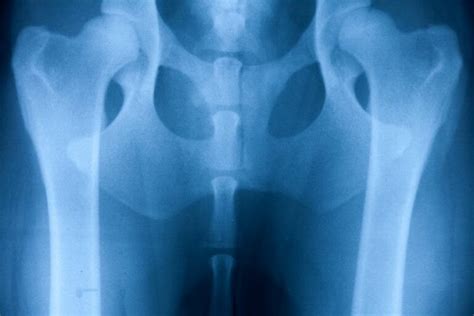

Dysplázia bedrového a lakťového kĺbu

Dysplázia bedrového a lakťového kĺbu - ochorenie, s ktorým sa stretávame v praxi pomerne často, postihujúce prevažne väčšie plemená psov. V rannom štádiu ochorenia sa dá postihnutým psíkom pomôcť niektorou z mnohých chirurgických metód. Metódu zvolí vždy skúsený chirurg na základe aktuálneho stavu a veku zvieraťa. Pokiaľ nie je možná chirurgická intervencia, ochorenie postupuje a psíkovi sa stav horší - následkom dysplázie je časom artróza, psík odmieta pohyb, ťažko vstáva, trpí bolesťou. Často je celoživotne odkázaný na medikamentóznu liečbu, ktorá kontroluje zápal a bolesť kĺbov a lieky, ktoré kĺb vyživujú. Medikamentózna liečba rieši len symptómy a spomaľuje proces degenerácie kĺbu, bohužiaľ nikdy nevedie k vyliečeniu. Netreba zabúdať ani na negatívne vedľajšie vplyvy podávaných liekov na celý organizmus.

Psíkom postihnutým dyspláziou vieme zlepšiť kvalitu života za pomoci fyzioterapie. Fyzioterapia ponúka celú škálu metód starostlivosti o psíky postihnuté dyspláziou. Našim cieľom pri starostlivosti o takýchto pacientov je v prvom rade obmedziť bolestivosť ochorenia, udržať resp. navrátiť fyziologický rozsah pohybu a udržať, prípadne zlepšiť, osvalenie. V závislosti od stupňa postihnutia a aktuálneho stavu pacienta každému vyrobíme na mieru vlastný terapeutický plán.